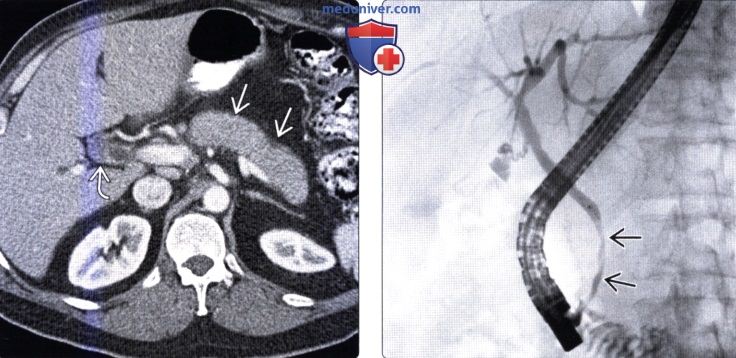

Фотографии и изображения, связанные с симптомами первичного склерозирующего холангита